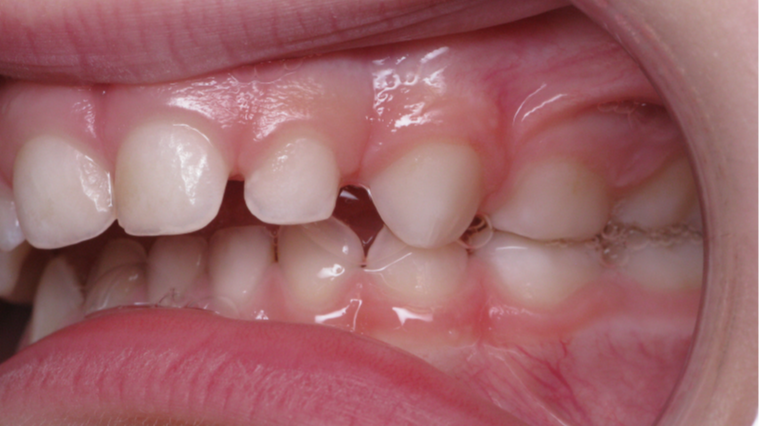

Décalage entre les dents d avant en arrière

surveillance évolution de la dentition pendant 4 ans

bilan début fin de traitement